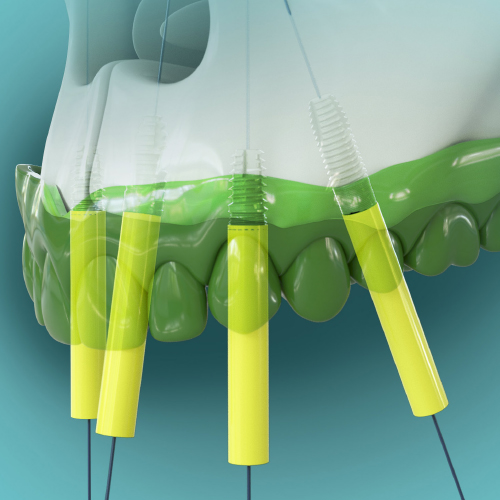

Dynamic Navigation for Dental Implants and Beyond—The Key to a Complete Digital Workflow

Robert W. Emery, BDS, DDS

Friday, March 29, 2024

This Compendium eBook offers a continuing education (CE) article that describes the various benefits and applications of dynamic navigation, and explains the workflows for implant surgery, including the workflow for full-arch reconstructions. Clinical examples are also provided in this arti...